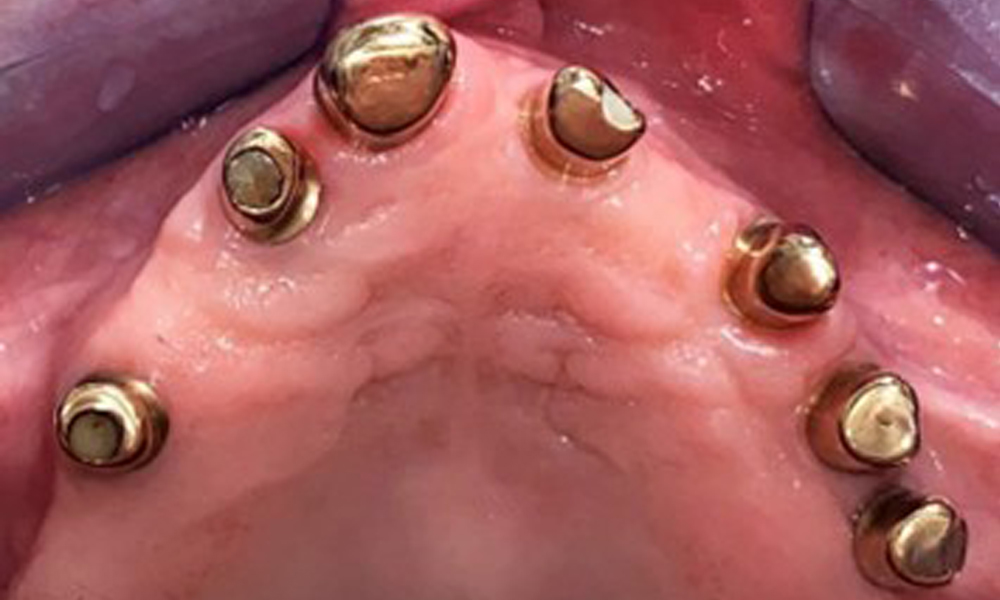

Der dentale Befund stellt sich wie folgt dar: Kombinierte herausnehmbare Implantat- und zahngetragene Teleskoparbeit auf Implantaten 15, 13, 21, 23, 24, 25 und Zahn 11 (Abb. 1, Abb. 2, Abb. 3). Im Unterkiefer ist die Patientin mit einem festsitzenden Zahnersatz versorgt. 37–34 sowie 45–47 haben suffiziente Brücken (Abb. 4). Kronenränder sind intakt, aktive kariöse Läsionen sind nicht vorhanden. An Zahn 43 zeigt sich eine Compositefüllung mit Randspalt. Im Unterkiefer liegen Rezessionen mit freiliegender Wurzeloberfläche zwischen 1 – 3 mm vor. Dies trifft auch für 11 zu.

Okklusalansicht: Oberkiefer mit herausnehmbarer, gaumenfreier Prothese.

Abb. 3 Okklusalansicht: Oberkiefer mit herausnehmbarer, gaumenfreier Prothese.